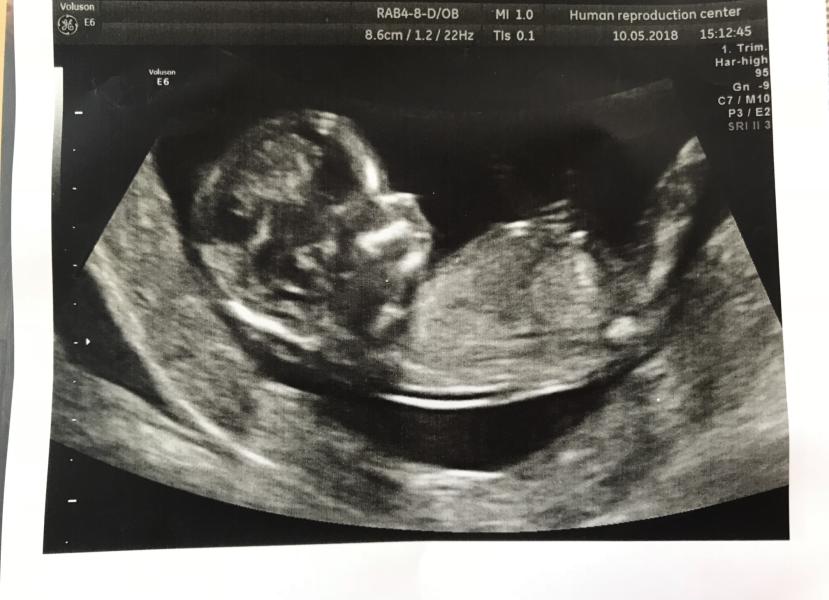

Первый скрининг прошли, все у нас хорошо, чему я очень рада! ☺️☺️☺️